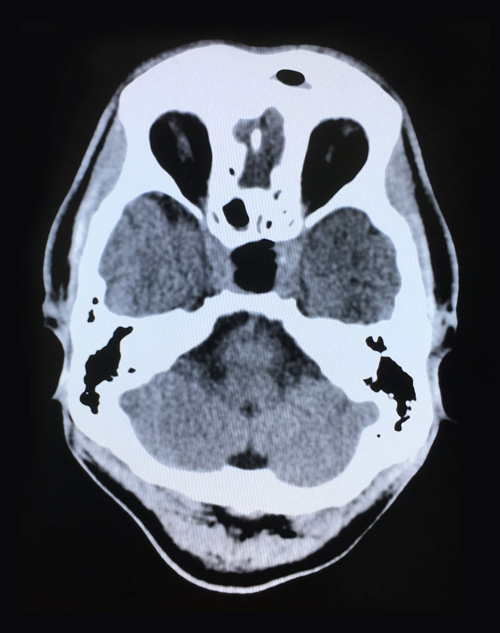

术后第二天影像:肿瘤切除干净,鞍内脑脊液填充

整个切除手术用时1小时左右,术中出血量很少,肿瘤切除干净。患者清醒后,被安全送到ICU(重症监护室)监护。经鼻蝶窦入路垂体瘤切除微创手术具有肿瘤暴露佳,创伤和危险性小,手术时间短、颅面外观无损伤,手术效果好等优点,但该手术方式对专家的技术水平也有着非常高的要求。